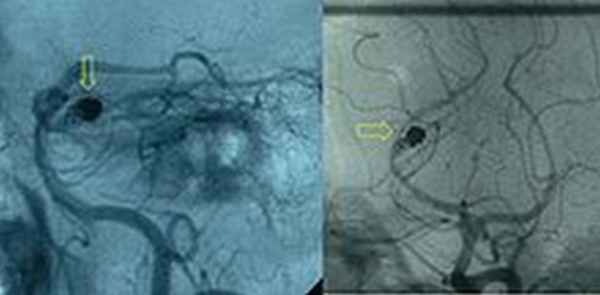

Рис.Артериограмма, демонстрирующая эндоваскулярно облитерированную аневризму (обозначена желтой стрелкой) задней мозговой артерии с остаточным аневризматическим мешком.